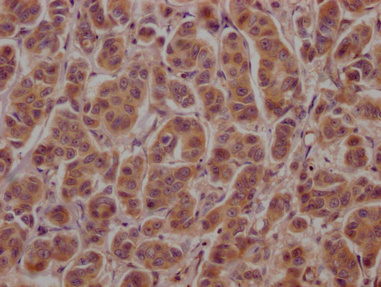

IHC image of CSB-PA002272LA01HU diluted at 1:100 and staining in paraffin-embedded human breast cancer performed on a Leica BondTM system. After dewaxing and hydration, antigen retrieval was mediated by high pressure in a citrate buffer (pH 6.0). Section was blocked with 10% normal goat serum 30min at RT. Then primary antibody (1% BSA) was incubated at 4°C overnight. The primary is detected by a Goat anti-rabbit polymer IgG labeled by HRP and visualized using 0.05% DAB.